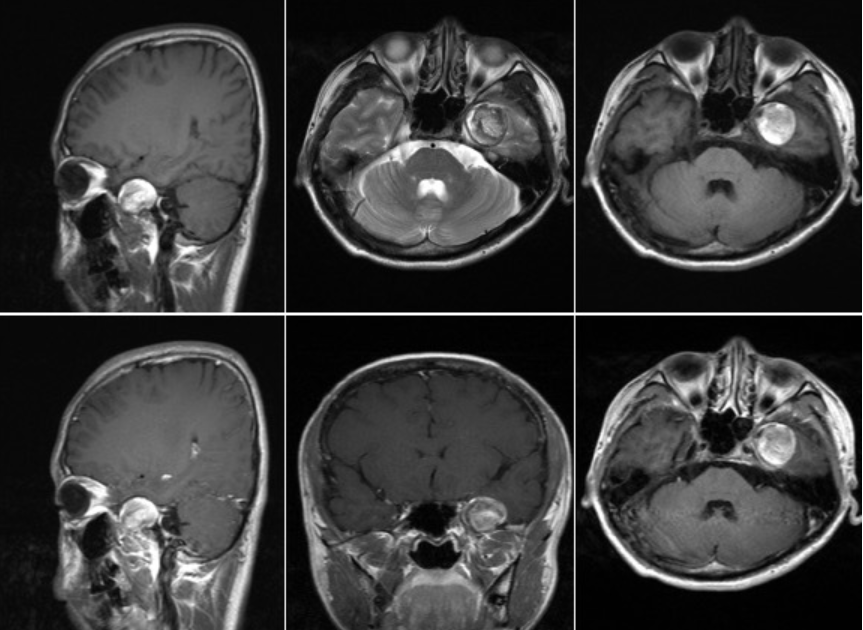

4.MRI:内含液态脂类物质,在T1WI表现为高信号是其特征性表现,有时也可因囊内含有毛发团等其他成分,呈高低混杂信号,T2WI多为略高信号。皮样囊肿破裂后蛛网膜下腔和脑室内有短T1、等T2脂肪信号。增强扫描肿瘤无强化。